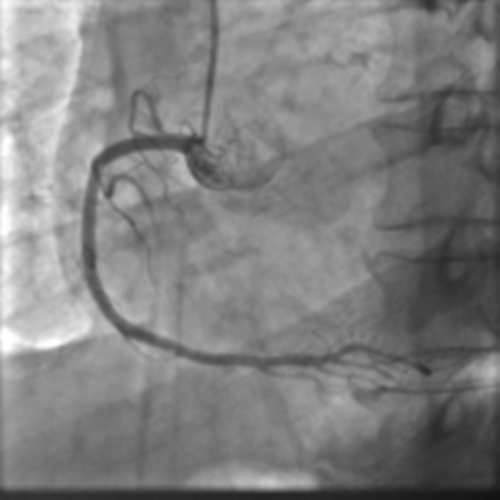

LCX(Left circumflex artery)

583d012476a401e39b0d21eb5b5f8837_1688025787_4604.png